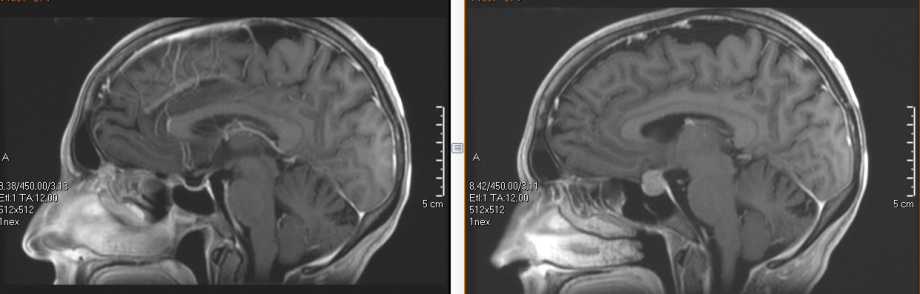

Cirugía de hipófisis

Las lesiones de la hipófisis han sido abordadas clásicamente a través de incisiones sublabiales y microscopio quirúrgico. En los últimos años se han desarrollado técnicas endoscópicas que aportan fundamentalmente dos ventajas: permiten utilizar los orificios naturales de la nariz evitando cualquier incisión y preservando mejor la mucosa nasal y ofrecen una visión mucho más cercana y nítida de la zona al poder introducir la óptica en el seno mismo del tumor. Estas dos ventajas se traducen en el paciente en postoperatorios más

confortables

y en resecciones tumorales más

amplias.

Nuestro equipo es pionero en la introducción de las técnicas endoscópicas para el tratamiento de lesiones selares con excelentes resultados.